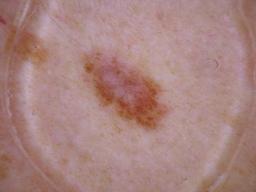

Training set from the ISIC 2018 Challenge.

[1] Noel Codella, Veronica Rotemberg, Philipp Tschandl, M. Emre Celebi, Stephen Dusza, David Gutman, Brian Helba, Aadi Kalloo, Konstantinos Liopyris, Michael Marchetti, Harald Kittler, Allan Halpern: "Skin Lesion Analysis Toward Melanoma Detection 2018: A Challenge Hosted by the International Skin Imaging Collaboration (ISIC)", 2018; arxiv.org/abs/1902.03368

[2] Tschandl, P., Rosendahl, C. & Kittler, H. The HAM10000 dataset, a large collection of multi-source dermatoscopic images of common pigmented skin lesions. Sci. Data 5, 180161 doi:10.1038/sdata.2018.161 (2018).